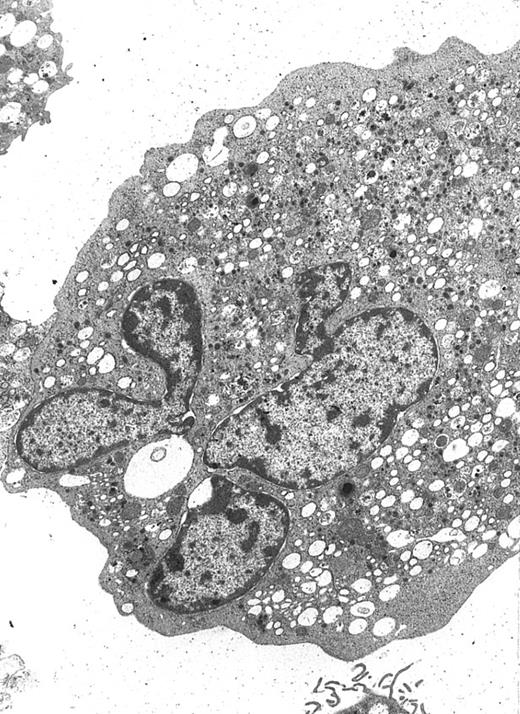

A well-differentiated megakaryocyte (original magnification × 3,080) generated from purified CD34+ cells cultured for 12 days in the presence of MIP-1α, IL-3, IL-6, IL-11, FL, SCF, and MGDF. A normal distribution of granules, mitochondria, and other cytoplasmic organelles is visible.